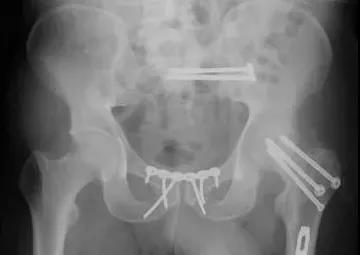

3)髋臼骨折(伤后5-7天)

- 人体最大的负重关节,精确复位可达到关节的最佳匹配,确保正常力学性能;

- 影像学移位程度大,不匹配>2mm--手术;

- 髋关节脱位,髋臼后壁骨折并股骨头骨折,复位后关节仍然不稳,或关节腔有游离骨块--手术。

并发症:异位骨化18-90%;股骨头坏死3-9%